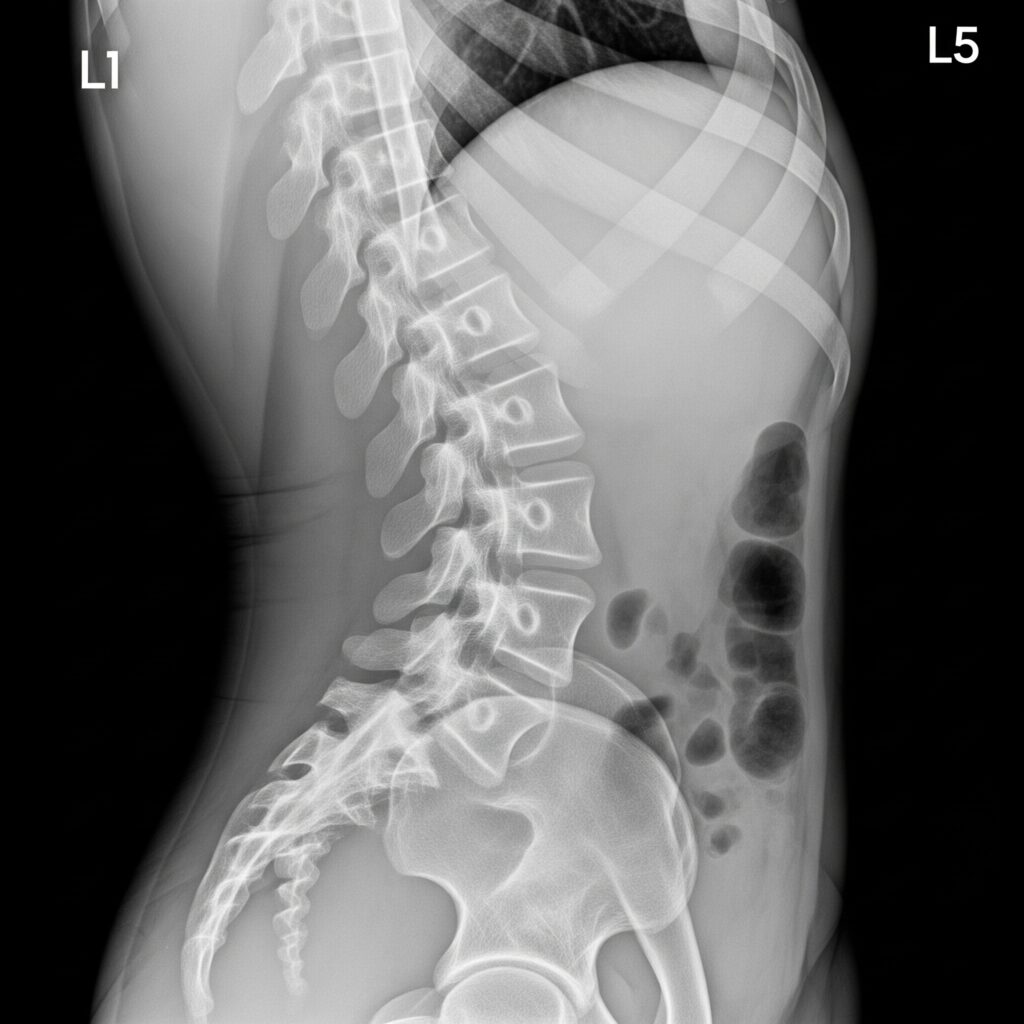

Asegure el cumplimiento normativo y proteja activamente la salud de su equipo con nuestro servicio de radiología. Realizamos estudios clave como Rayos X de tórax y columna, indispensables para la vigilancia de riesgos en industrias como la minería, construcción y manufactura.

Nuestra tecnología flat panel, operada por técnicos radiólogos certificados y con equipos siempre calibrados, nos permite entregar resultados confiables rápidamente, facilitando la gestión de la salud y la prevención de enfermedades laborales.

Rayos x de Columna

Nuestra tecnología

flat

panel

Otorga ventajas frente a la radiografía convencional.

Precisión Superior: Imágenes de alta definición que revelan detalles cruciales para un diagnóstico certero.

Eficiencia Inmediata: Resultados al instante y expedientes electrónicos que eliminan la espera y simplifican la gestión.

Máxima Seguridad: Tecnología de baja dosis que protege el bienestar y la salud de sus colaboradores.